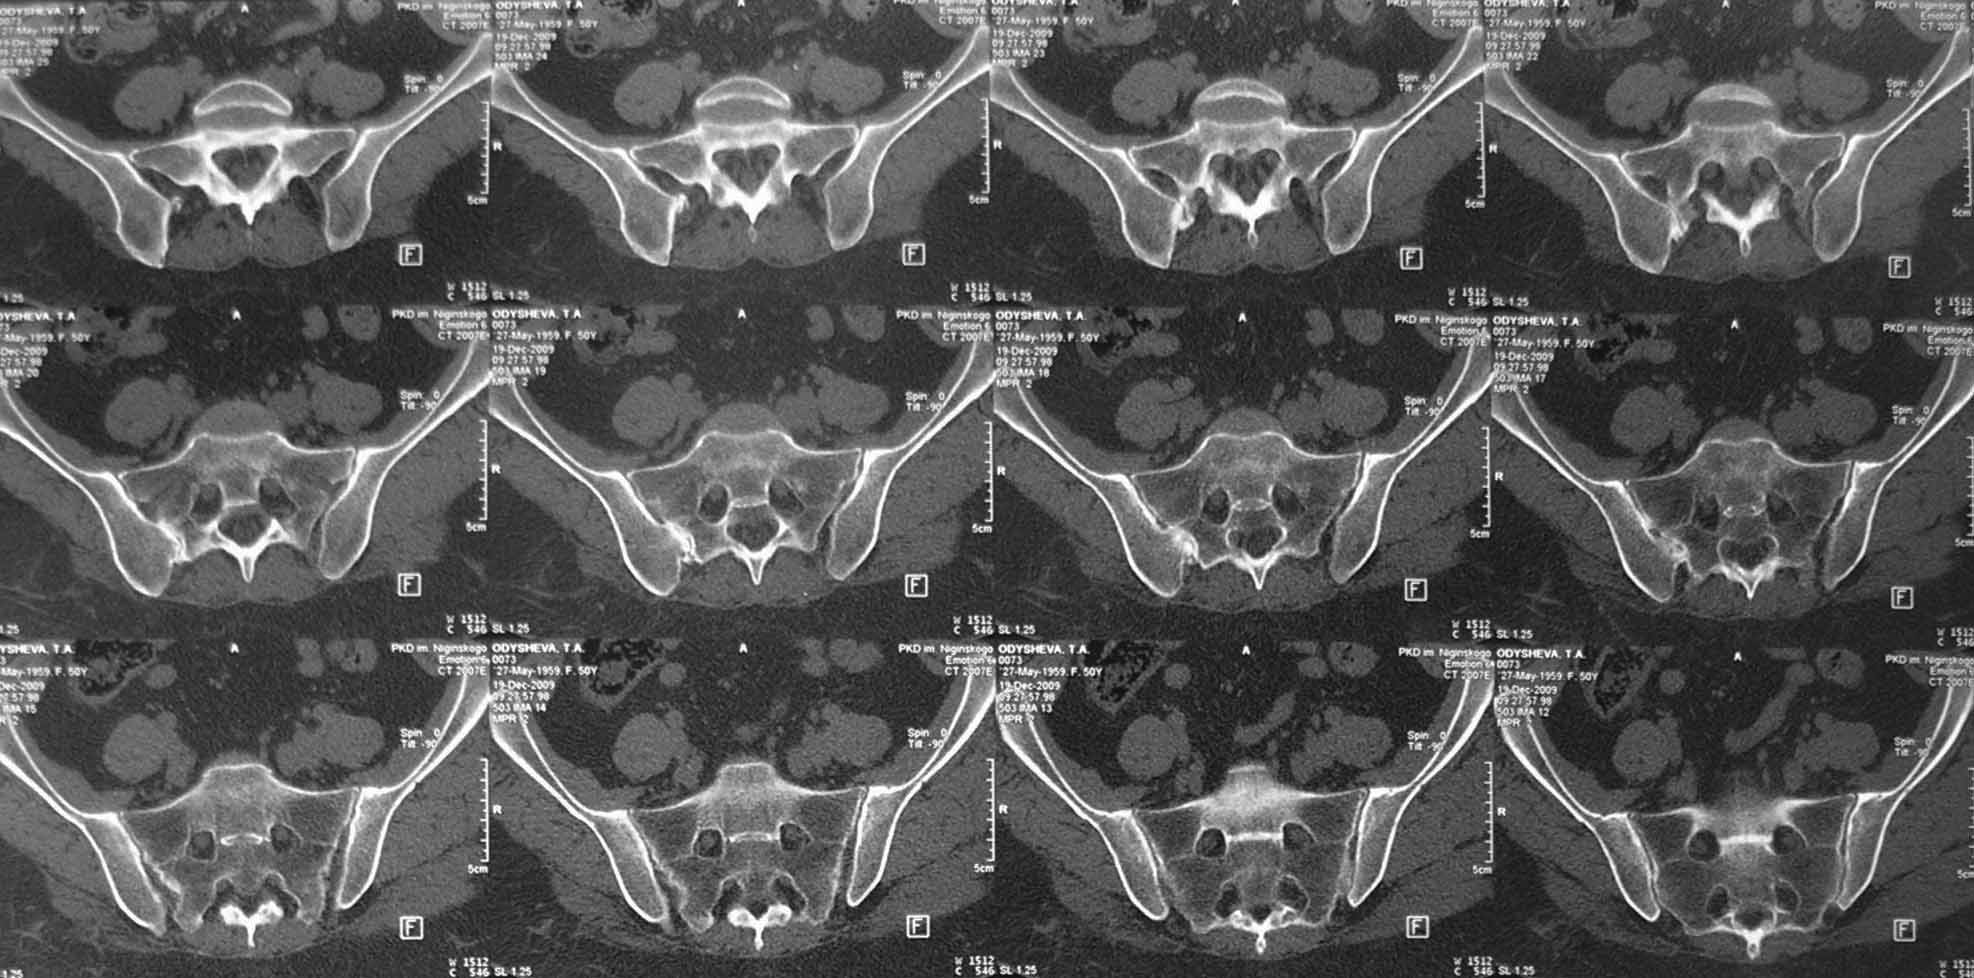

Уважаемые коллеги, пожалуйста выскажите свои мысли по поводу клинического случая:

пациентка 51 года страдает болями в области правого крестцово-подвздошного сочленения.

Боли отмечала и раньше, но они беспокоили не сильно, справлялась мазями, отдыхом. В течении

последних пяти лет боли выраженного характера, не зависящие от положения тела,

усиливающиеся при движениях, при резких движениях и кашле стреляющего характера, не

иррадиирую. Ходит с трудом при помощи костылей. Движения ограничены из за боязни боли.

Сиптомы натяжения отрицательны. Последние 3 года на инвалидности (была врачем).

Неоднократно проходила курсы консервативного лечения по поводу остеохондроза

позвоночника (сосудистые препараты, НПВС, всевозможные блокады,

массаж)санаторно-куротное лечение с незначительным и очень ограниченным эффектом. На

Р-граммах, КТ, МРТ остеохондроз не выраженный, грыж дисков нет. Лечилась у неврологов,

консультирована вертебролагами в разных НИИТО. В 2009г установлен диагноз - сакроилеит

справа. На представленных КТ имеется гипертрофия заднего отдела правой подвздошной кости с

образованием контакта с задней поверхностью крестца. В январе 2011 года выполнена попытка

удаления гипертрофированного участка подвздошной кости. удаленные участки кости

исследованы гистологически - губчатая кость с элементами гиалинового хряща. После

операции положительного эффекта не получено. На контрольной КТ от 04.2011 обнаружено что,

желаемого результата операции не получено(интересующий участок удален частично), при

этом имеется расслоение заднего отдела правой подвздошной кости. Сейчас клиника таже

самая, признаков воспаления внешне нет, по анализам тоже нет, туберкулеза нет и бруцеллеза

тоже нет.